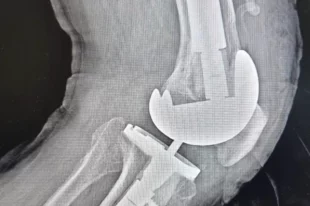

Операция сложная: в Мурманске провели ревизионное эндопротезирование колена

15:25

Это операция по замене установленного ранее протеза сустава на новый.

ЗДОРОВЬЕ